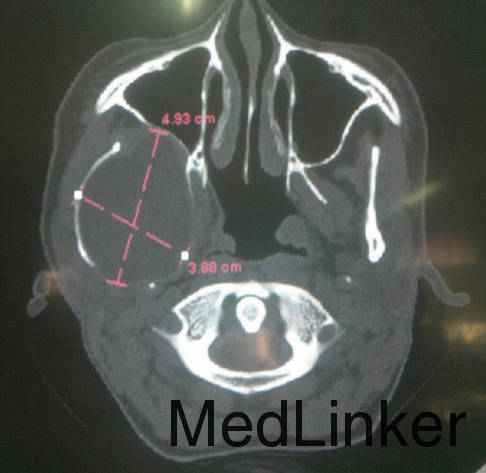

检查发现面部对称,开口度正常,右侧颞下颌关节区可扪及柔软肿块,右侧颞下颌关节运动较左侧减弱,颈部淋巴结无明显肿大。 影像学检查发现右侧颞下颌关节可见一完整4.9*3.8cm大小溶骨性囊性病变,内含积液。

全麻下完整切除囊性病变,送检结果显示为包虫囊肿。患者术后两年复诊未见复发迹象。

包虫囊肿具有地区性,多发生于畜牧区,可作为鉴别诊断依据。大多数包虫囊肿发生于肝脏,鲜有报道发生于颞部,此病例中为目前报道的第四例且体积最大的颞部包虫囊肿。囊肿手术切除过程中一定要小心完整切除,避免囊壁破损囊液外漏造成复发。